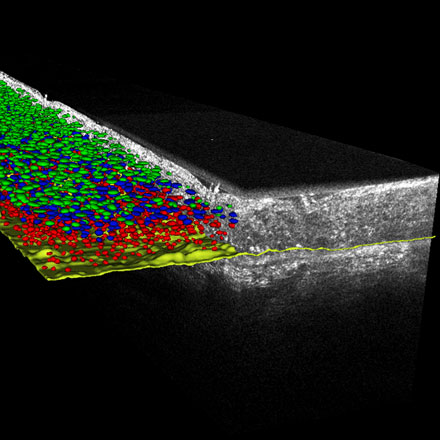

Line-field confocal optical coherence tomography (LC-OCT) is an imaging technique based on a combination of reflectance confocal microscopy and time-domain OCT. It can generate cellular-resolution vertical images, horizontal cross-sectional images, and three-dimensional (3D) images, yielding the possibility for optical biopsies of skin tissue in vivo and in real time.

The development of artificial intelligence (AI) algorithms has enabled the utilization of the information contained in LC-OCT images to provide quantitative metrics. These metrics can be used to discriminate between healthy and pathological skins, specifically in the context of monitoring skin cancer. Finally, Ogien presents how molecular information from the skin can be probed noninvasively under the guidance of LC-OCT by introducing a platform for co-localized ex vivo LC-OCT and confocal Raman microspectroscopy, yielding an extensive characterization of skin tissues, both molecular and morphological.